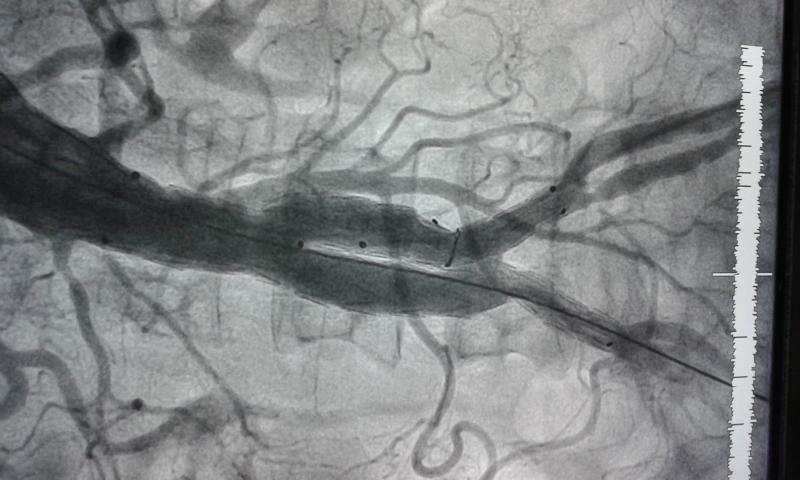

Picture of the infraabdominal aortic aneurysm repair using a bifurcation graft to give proper flow to both the iliac arteries is shown below

Before and after repair

The above is the aneurysm and below is the scan after repair